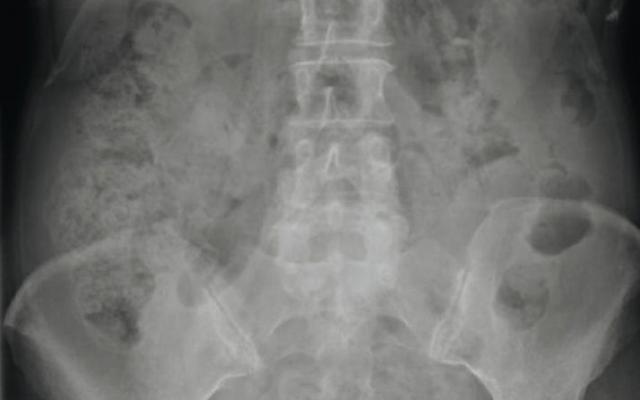

A 66-year-old woman presented with fever and acute pain in her lower back and left hip. She used prednison for arteriitis temporalis. Abdominal radiography revealed no signs of free intraperitoneal gas, but instead a radiolucent area below the spleen suggesting free retroperitoneal gas. This was confirmed by CT-scan of the abdomen and surgery, when a diverticulitis of the colon descendens with retroperitoneal perforation was diagnosed.